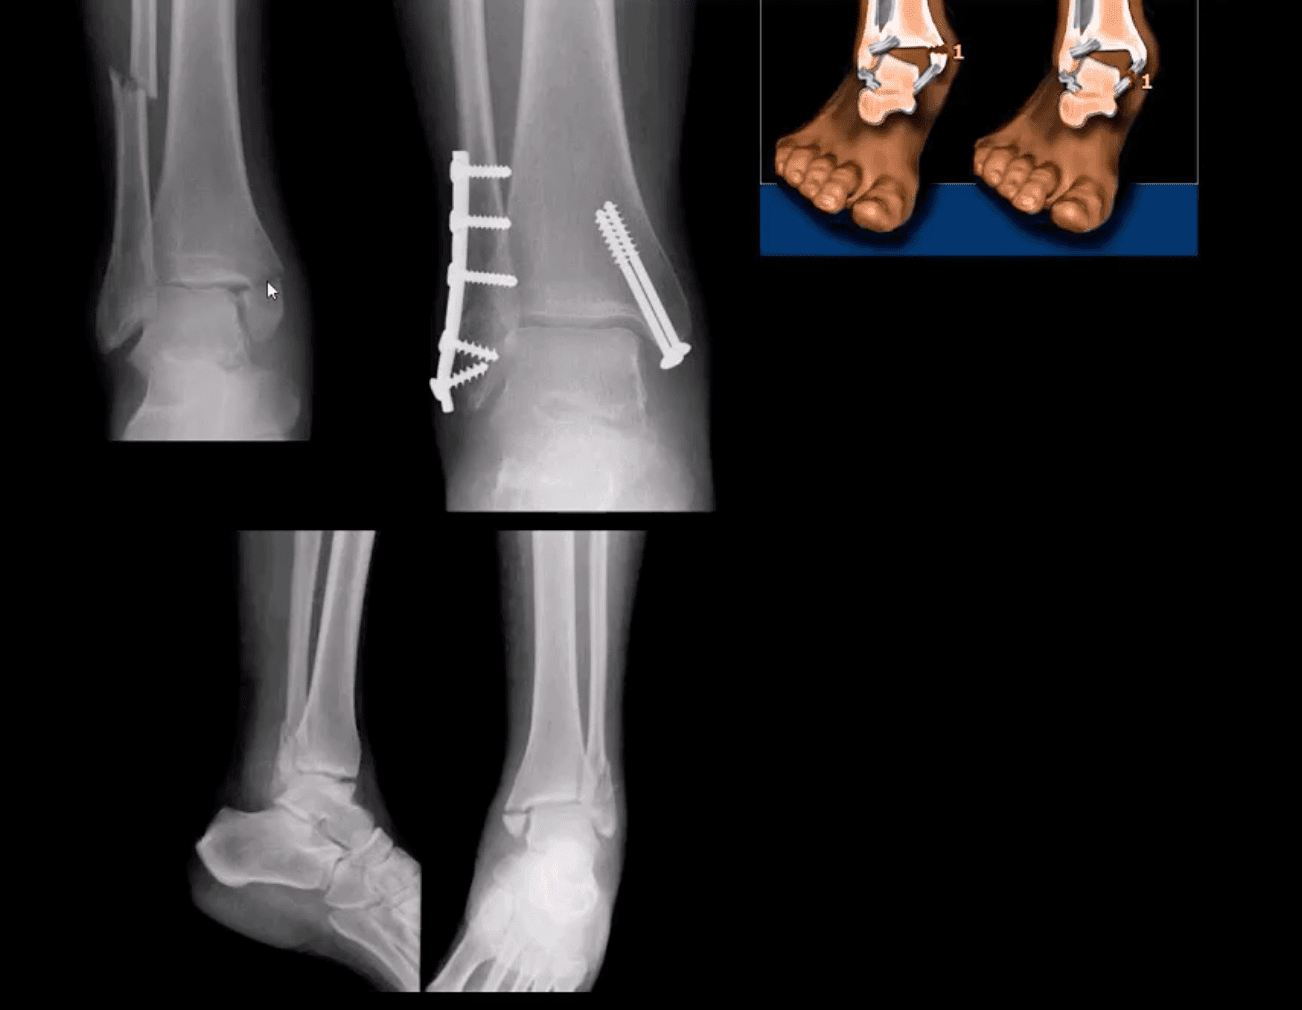

Bimalleolar & Trimalleolar Fx

- Above top images Bimalleolar Fx v. unstable, result of pronation and abduction/external rotation. Rx: ORIF.

- Trimalleolar Fx: 3-parts ankle Fx. Medial and lateral malleolus and avulsion of theposterior aspect of tibial plafond. More unstable. Rx: operative

Tillaux Fx

- Pediatric Fx affecting older child when medial side of the physis is closed or about to close with lateral side till open. Avulsion by anterior tibi-fibular ligament. Complications: 2nd dry/premature OA. Rx: can be conservative if stable by boot cast immobilization.